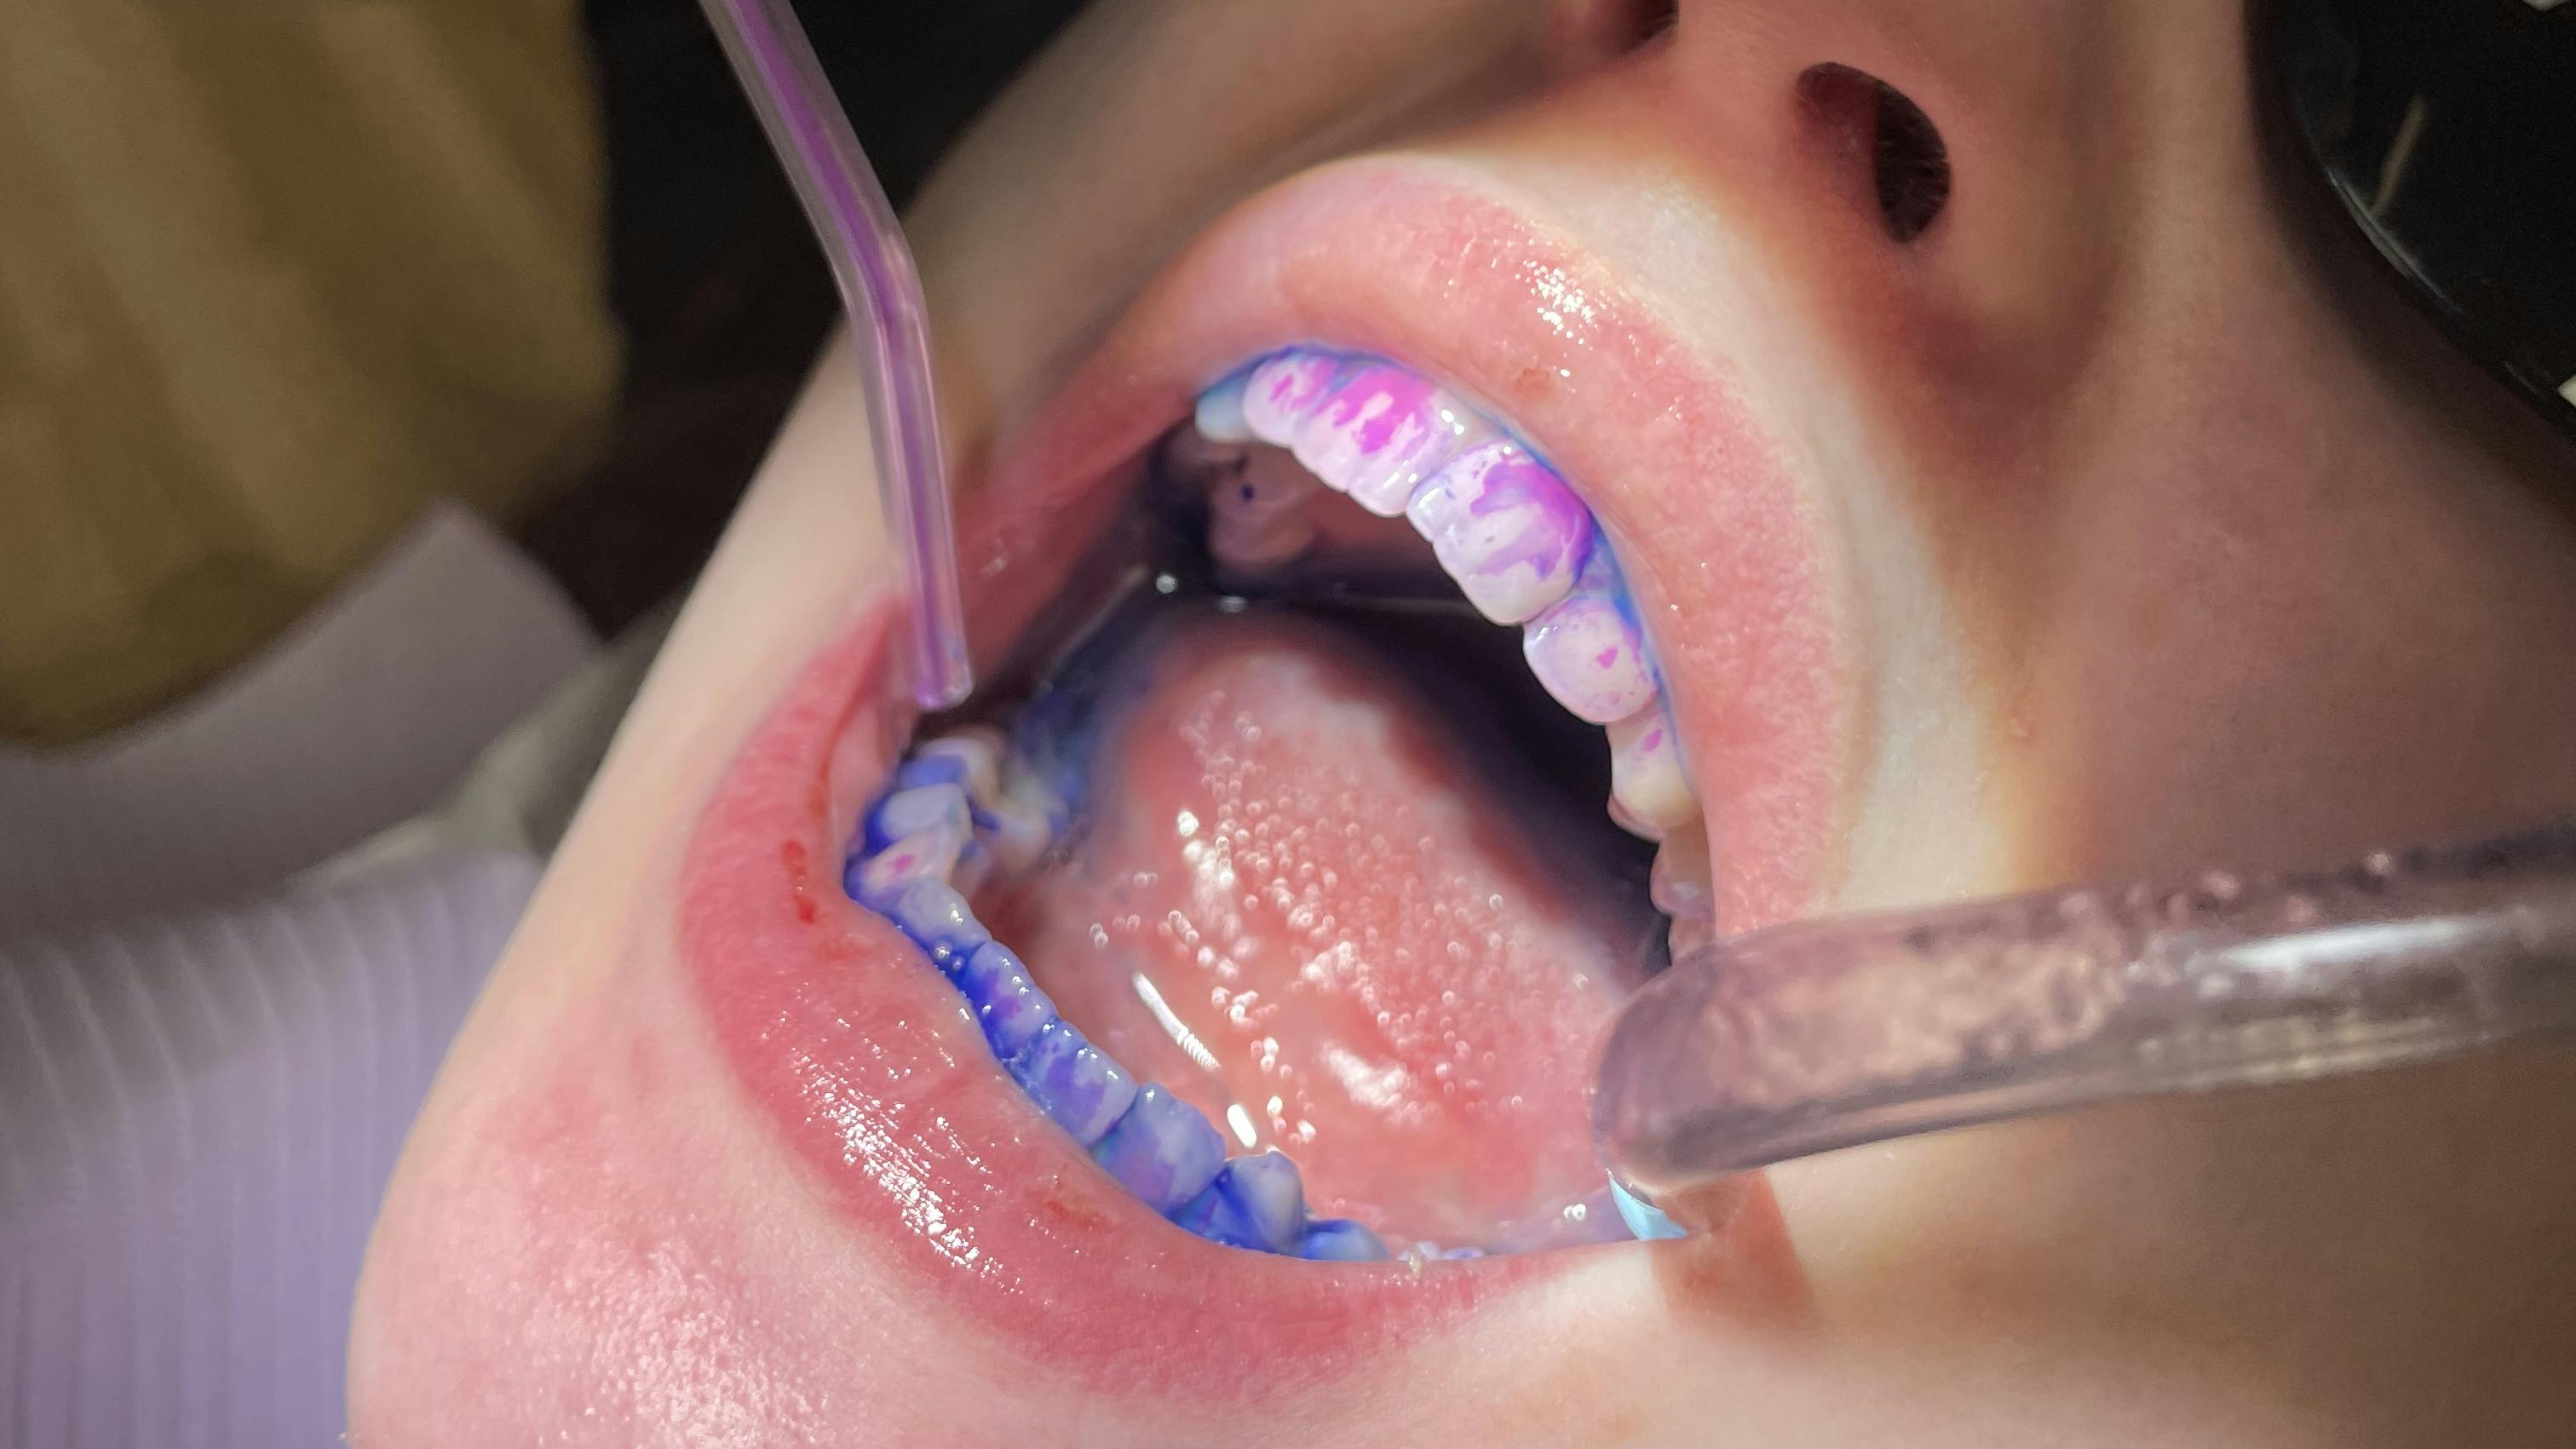

Shortly thereafter, two- and three-tone disclosing solution agents became available. Two-tone disclosing agents stain in two colors, blue and red, with the biofilm that has been sitting on the patient’s teeth for quite some time turning blue and newer biofilm turning red. Three-tone disclosing agents stain old and new biofilm similar to two-tone disclosing agents, but they also highlight the cavity-producing bacteria a purple color. No matter which disclosing solution you choose to apply, the end goal is the same: highlight the plaque while motivating and encouraging the patient to improve their oral hygiene regimen.1-7

Introducing a disclosing agent to highlight a patient’s biofilm accumulation can be done very efficiently. First, inquire if the patient has recently brushed after eating and drinking. This is important so that deposits of biofilm accumulation can be more easily recognized. Next, apply the disclosing agent. If it is a liquid, instruct the patient to swish the agent around in their mouth and then expectorate after rinsing. You may need to suction any remaining disclosing liquid from the patient’s oral cavity.

When using a gel disclosing agent, rub the gel onto the patient’s teeth with a cotton-tip applicator and then rinse it away. Tablet-formed disclosing agents are chewed until they become liquid. The patient can swish the agent around in their mouth and then expectorate after rinsing. Again, any remaining solution may need to be suctioned from the mouth.

After all disclosing agents have been applied, we can codiscover with the patient to see the biofilm remaining and note where it is located. Ask open-ended questions to help the patient recognize how the biofilm accumulation might still be present, even though the patient may have believed they removed it all during their oral hygiene regimen. Assure patients that the highlighting benefits of disclosing agents are only temporary; the patient can remove it by brushing it away.1